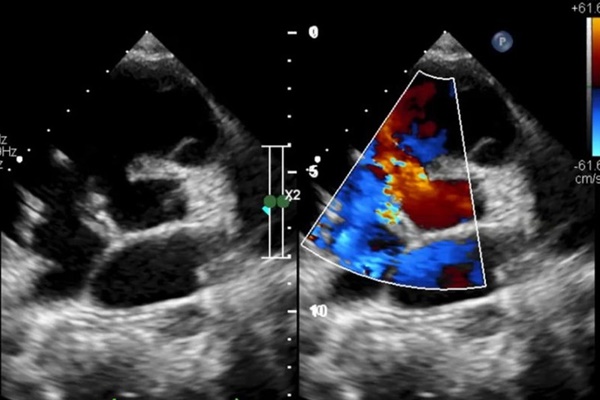

Hình ảnh siêu âm trước khi mổ cho bệnh nhi. Ảnh: BVCC

Trên các kết quả thăm dò, siêu âm tim thông liên thất quanh màng lan vào buồng nhận. Kích thước lỗ thông lớn, đường kính lỗ khoảng 16 mm, shunt trái phải, chênh áp cao. Tim giãn to, các chỉ số tim như đường kính thất trái là 61.